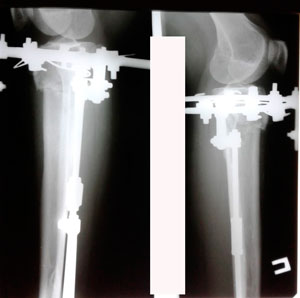

Исходник 32 года. Якутия

Дата операции - 05.02.2020г